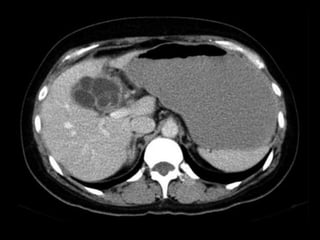

HIPERPLASIA NODULAR FOCAL